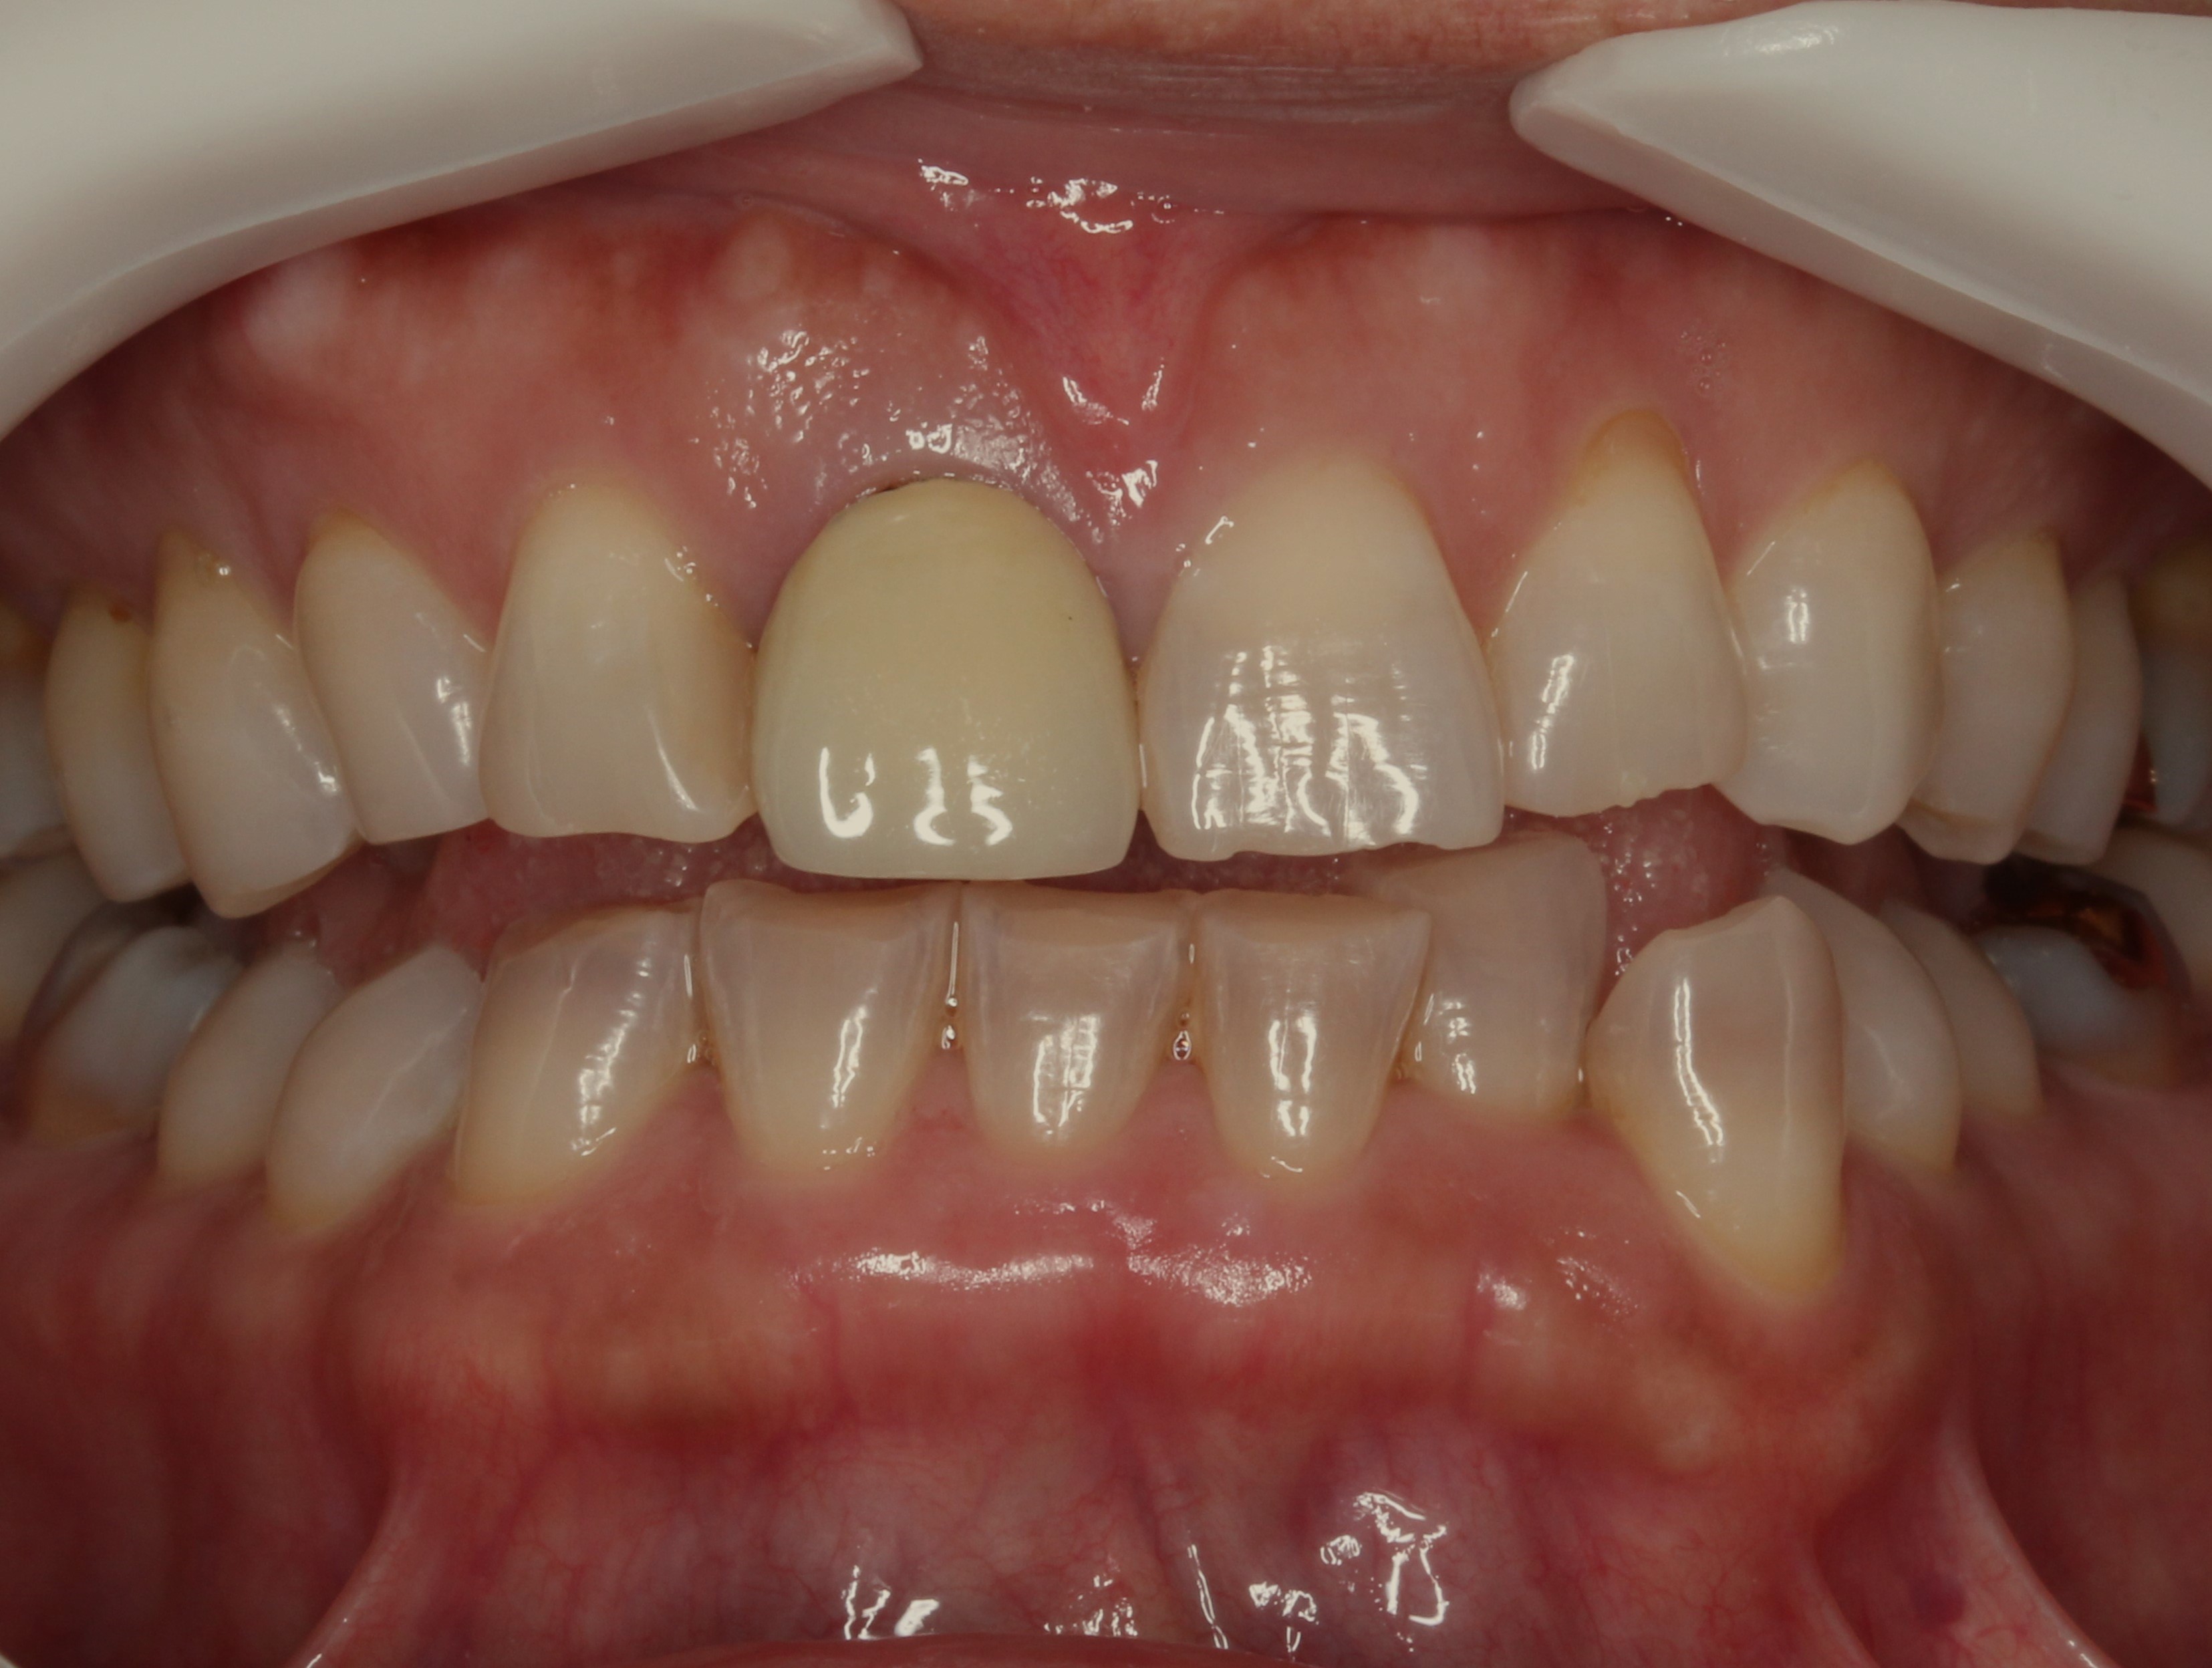

お口の中を見てみると

このような状態でした。

どこが差し歯かわかりますよね?

矢印のこちらの歯です。

歯の根元が黒くなり、

歯の色が合わなく1本だけ浮いて見えます。

また歯の形も膨らみが強く、いかにも「作った歯」という感じです。